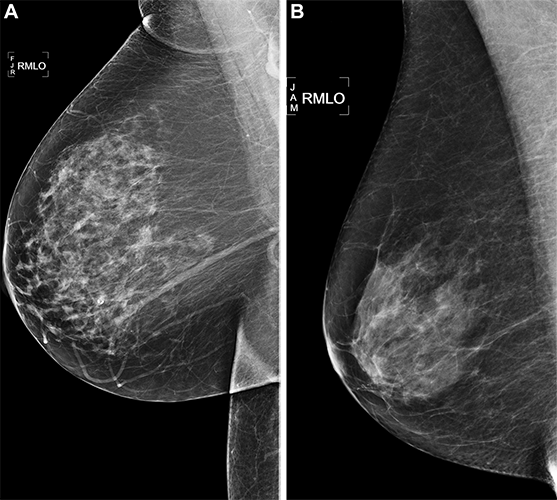

Right medial lateral oblique (RMLO) screening mammograms show negative results from 2016 in (A) a 73-year-old woman with Mirai artificial intelligence (AI) risk score with more than 90th percentile risk who developed right breast cancer in 2021 at 5 years of follow-up and (B) a 73-year-old woman with Mirai AI risk score with less than 10th percentile risk who did not develop cancer at 5 years after 5 years of follow-up.